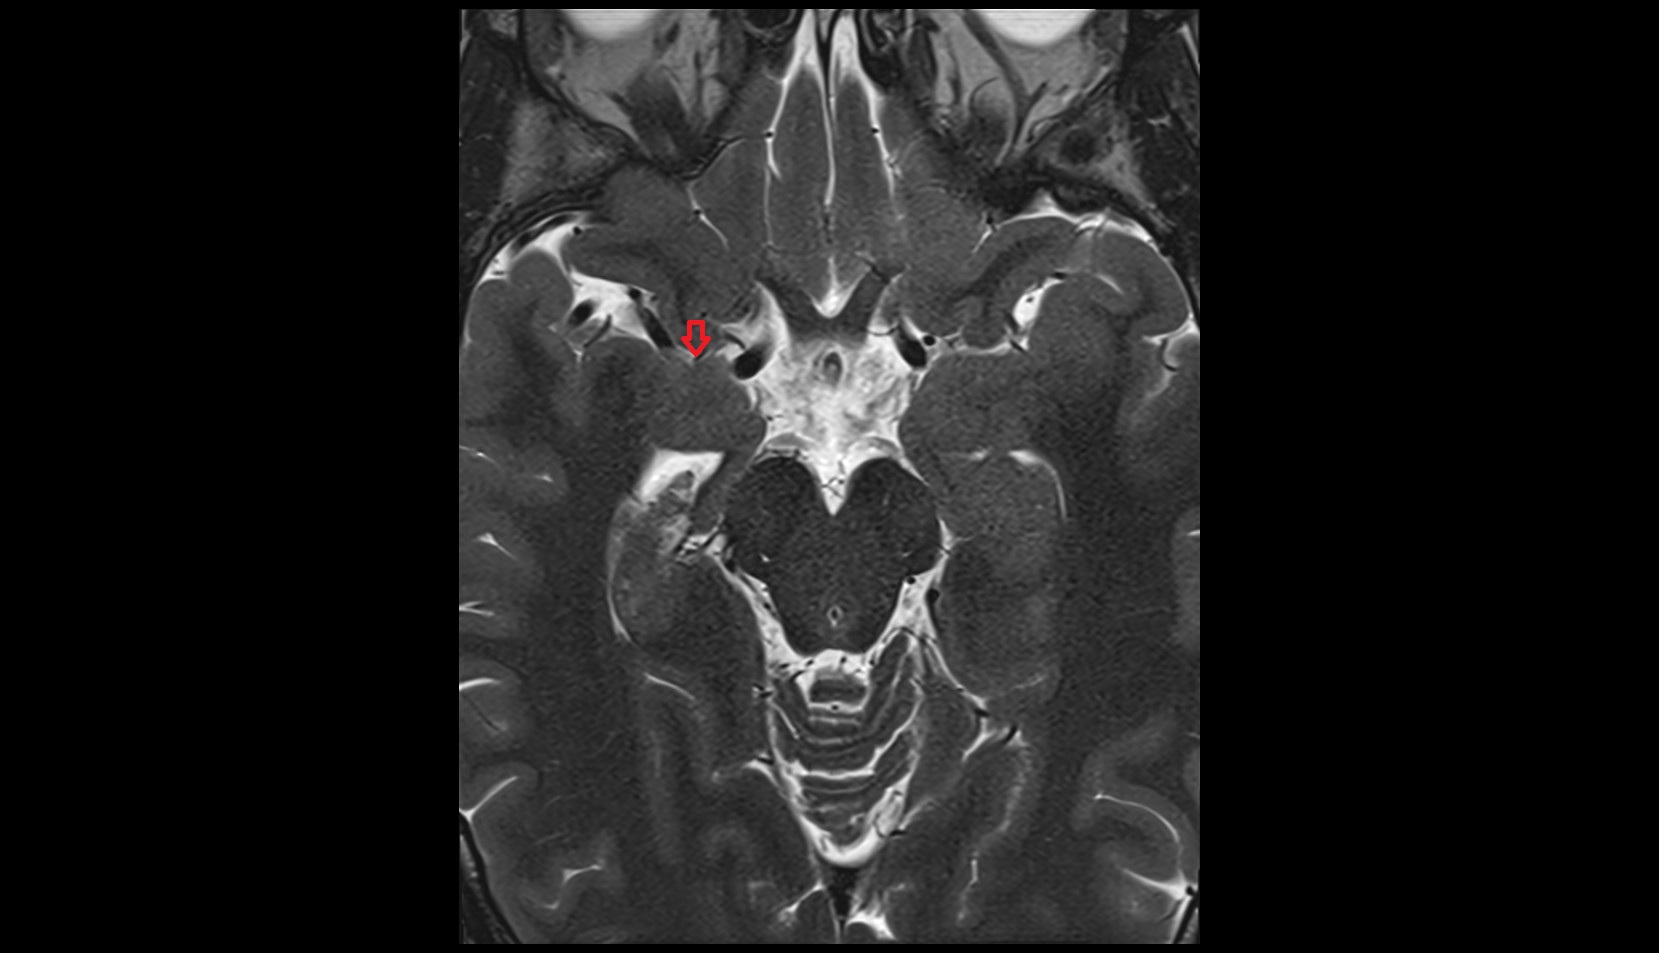

- Lateral aperture of fourth ventricle (foramen of Luschka)

- Lateral aperture of the fourth ventricle